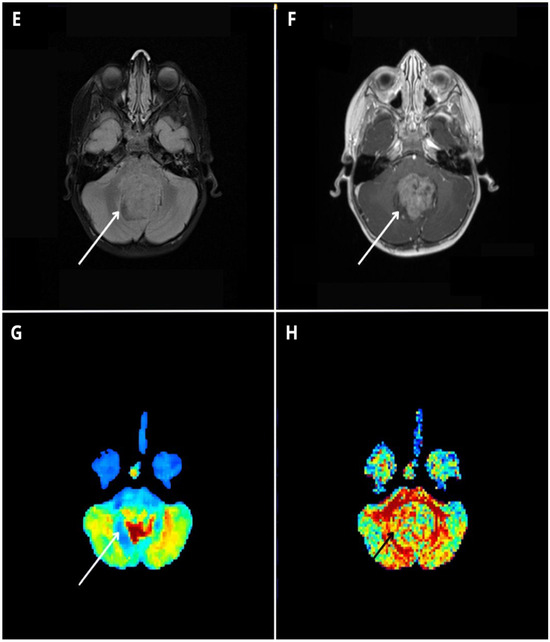

Figure 5.

Diffusion kurtosis imaging-based findings to discriminate between pediatric posterior fossa tumors. MRI images are of a 7-year-old girl affected by a WHO grade I pilocytic astrocytoma (A–D), a 10-year-old boy affected by medulloblastoma (E–H), and an 8-year-old boy affected by a WHO grade II ependymoma (I–L). Native MPRAGE T1 post-contrast images (B,F,J) show three contrast-enhancing posterior fossa tumors located within the fourth ventricle, presenting a variable proportion of solid and cystic components. Qualitative evaluation of the mean kurtosis (MK) color maps (C,G,K) reveals significant differences between the lesions, with the pilocytic astrocytoma (PA) presenting relatively lower MK values ((C), white arrow), the ependymoma (EP) presenting intermediate MK values ((K), white arrow), and the medulloblastoma (MB) presenting high MK values compared with the other two lesions ((G), white arrow). Whole tumor labeling (green label) on the co-registered contrast-enhanced MPRAGE (B,F,J) and MK maps (C,G,K) yielded quantitative whole-tumor MK values of 0.40, 0.55, and 1.04, for PA, EP and MB respectively.

Post hoc Benjamini–Hochberg-corrected t tests showed all DKI metrics were significantly different between medulloblastoma and pilocytic astrocytoma (p < 0.001 for all metrics, asterisk). Moreover, RK, MK, and AK were significantly different between medulloblastoma and ependymoma (p < 0.012, p < 0.001, and p < 0.001, respectively, triangle), and AK, FA, and MD were significantly different between pilocytic astrocytoma and ependymoma (p < 0.048, p < 0.001, and p < 0.004, star, respectively). Thus, different specific DKI-derived diffusion metrics were useful in discriminating among specific tumor subtypes.